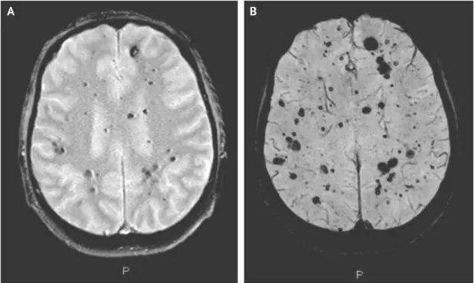

然而当他们切开牛的头骨时,看见了惊人的一幕。只见牛的大脑已经失去了原本光滑完整的样貌,取而代之的是一团布满蜂窝状孔洞的大脑。但就在人们一头雾水的时候,人的身上也出现了一样的症状,当时英国将这种病命名为疯牛病。